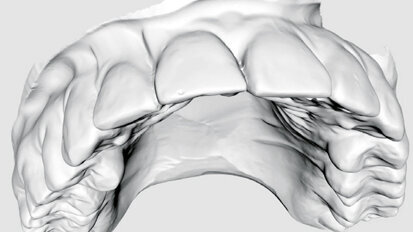

Nový úsměv za jeden den

Čt. 28. května 2020